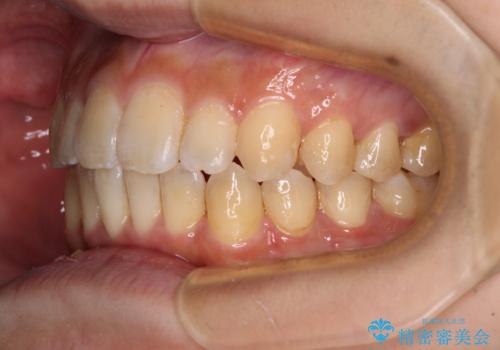

オープンバイトと目立つ銀歯 インビザライン矯正とセラミック修復治療

- 奥歯の目立つ銀歯と上下前歯の叢生と隙間を気にして来院された患者様です。

開咬の治療は、前歯を閉じるように動かすとともに、上下臼歯を圧下(骨内にめり込ませる)させることで進めて行きます。

インビザラインは臼歯の圧下を効果的に行えるため、インビザラインを用いて矯正治療を行うこととしました。